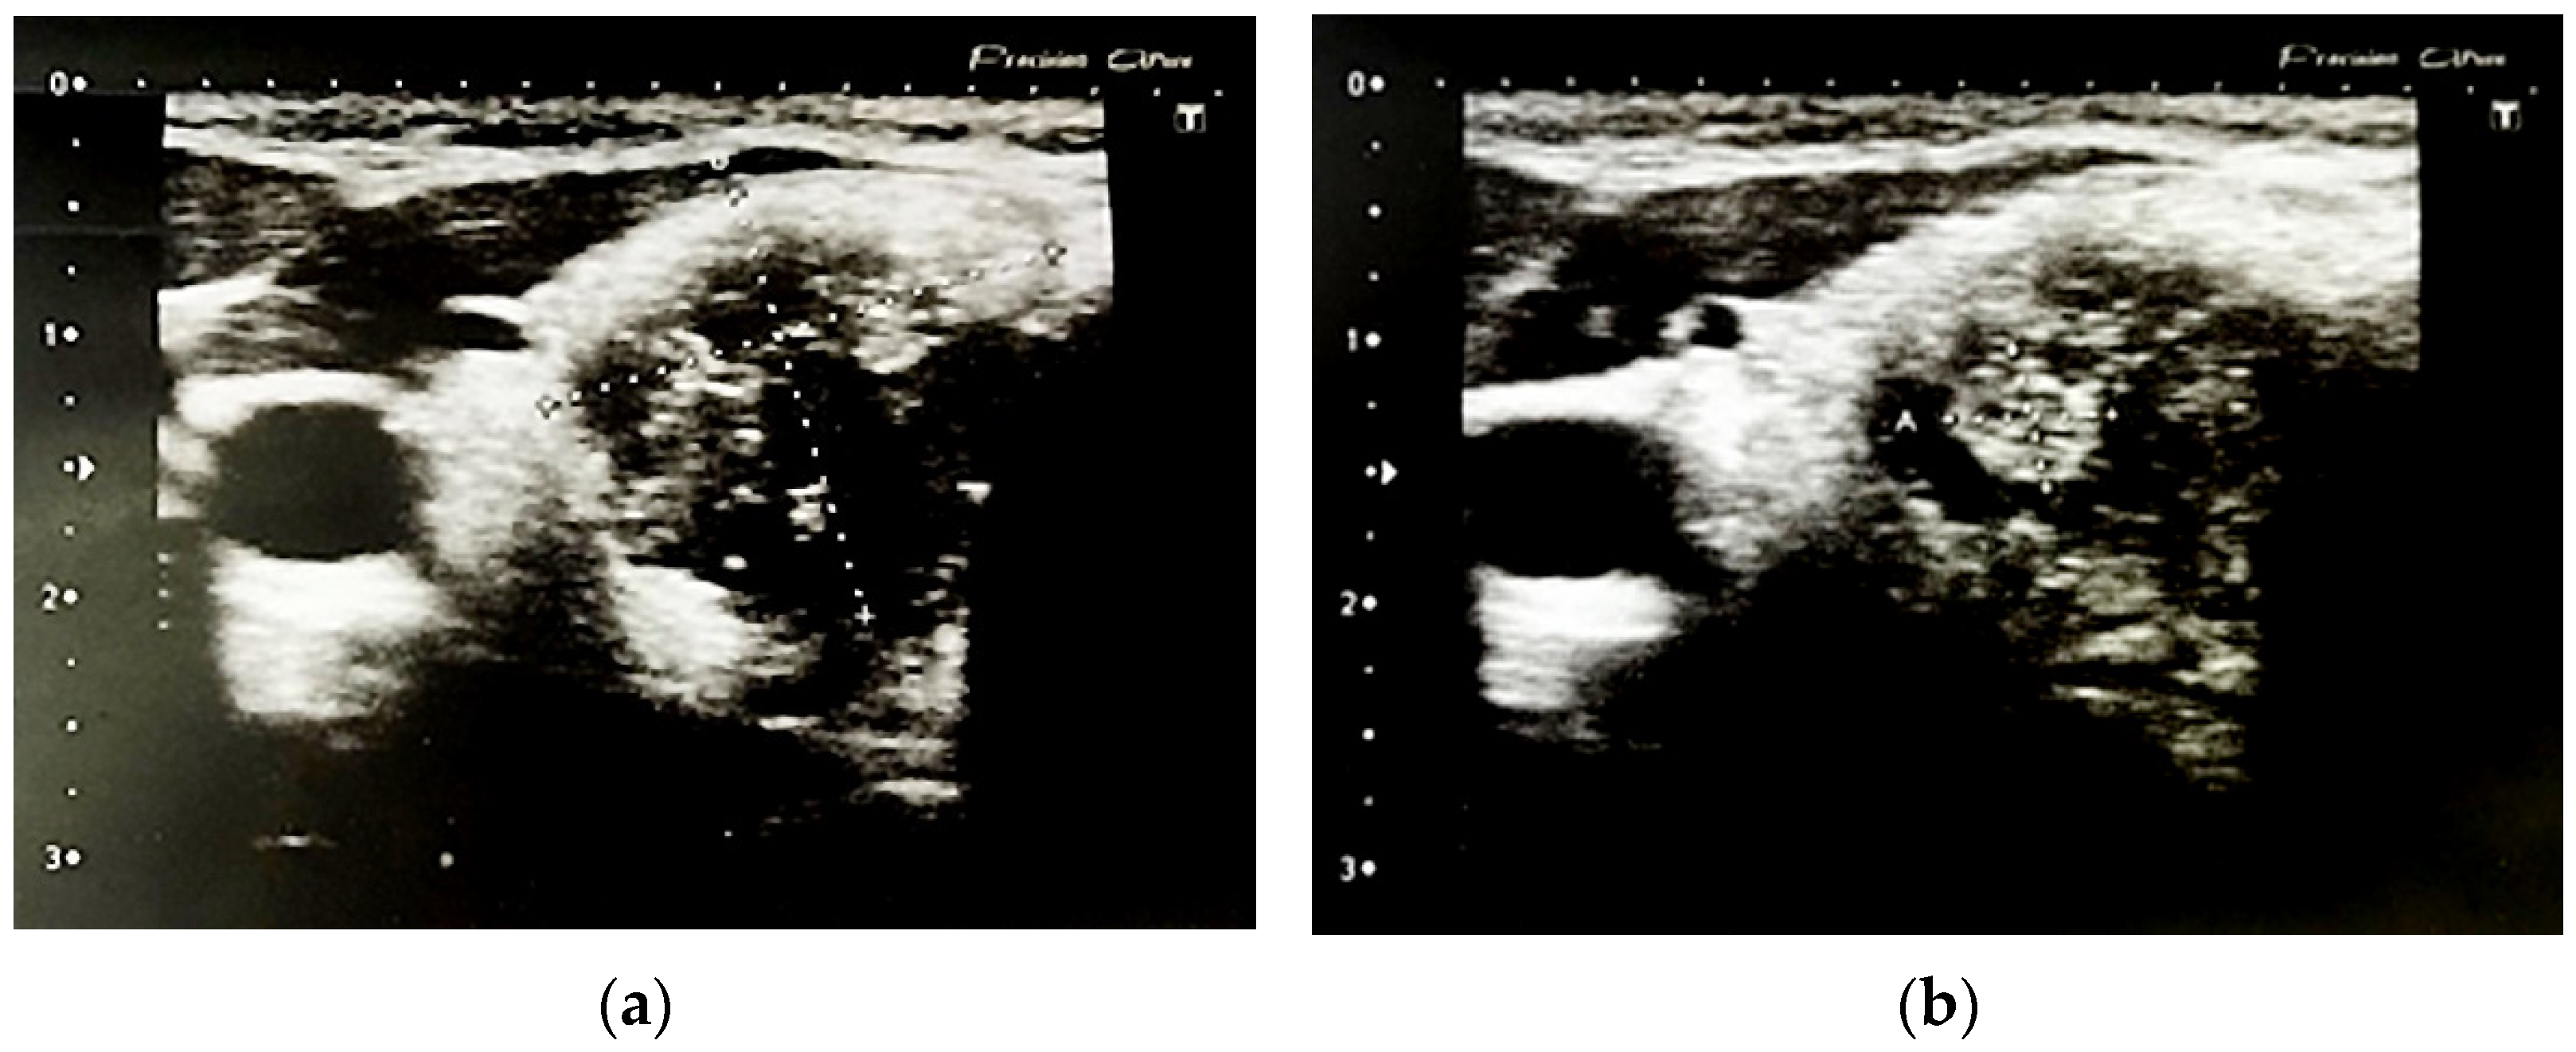

2.3. Thyroid Ultrasonography, Elastography and Fine Needle Aspiration Biopsy